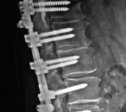

<figcaption>Spinal Rods & Screws</figcaption>